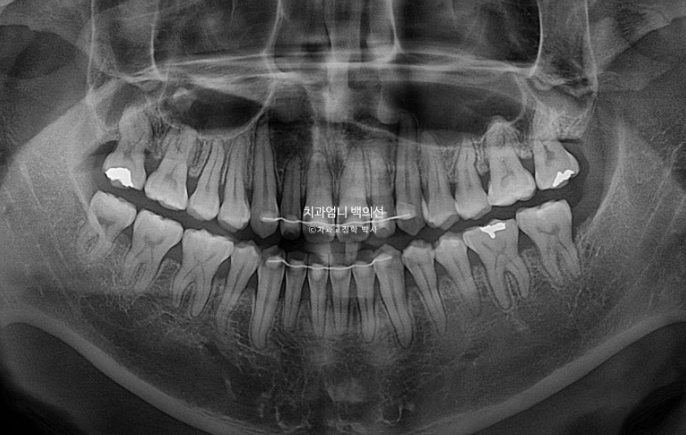

파란화살표에 작은어금니 하나가 없습니다.

치료계획을 크게 보면 아래 전치치아를 뒤로 밀면서 어금니 교합을 1급으로 맞추고 위 앞니가 아래 앞니를 덮도록 하는 것이 메인입니다.

이를 위해 아래 왼쪽 사랑니는 발치를 하고 작은어금니 하나가 없는 반대쪽은 사랑니 발치를 하지 않습니다.

사랑니 공간으로 치아들을 밀 때 불리하긴 하지만 좌우 치아 갯수 밸런스를 맞추기 위해서입니다.

치근흡수는 없고 치근평행도는 좋습니다.

추가적인 발치나 양악수술 없이도 절충치료만으로 좋은 효과를 볼 수 있습니다